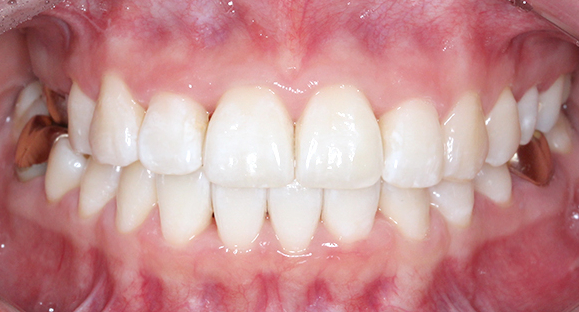

[4개월 교정이 끝난 모습]

4개월만에 가지런하게

치열이 바뀐 모습입니다.

생각보다 더 빠르게

교정이 끝났는데요 ^_^

치아 모양도 고르고 예쁘게

잘 교정되었습니다.

전체 교정만큼 고생하지 않고

빠른 기간동안 개선되어

환자분도 굉장히 만족하셨습니다.

하지만 치아는

늘 제자리로 돌아가려는

성질이 있기 때문에

유지장치를 잘 해주셔야

가지런한 치아를

오랫동안 유지할 수 있습니다 :)